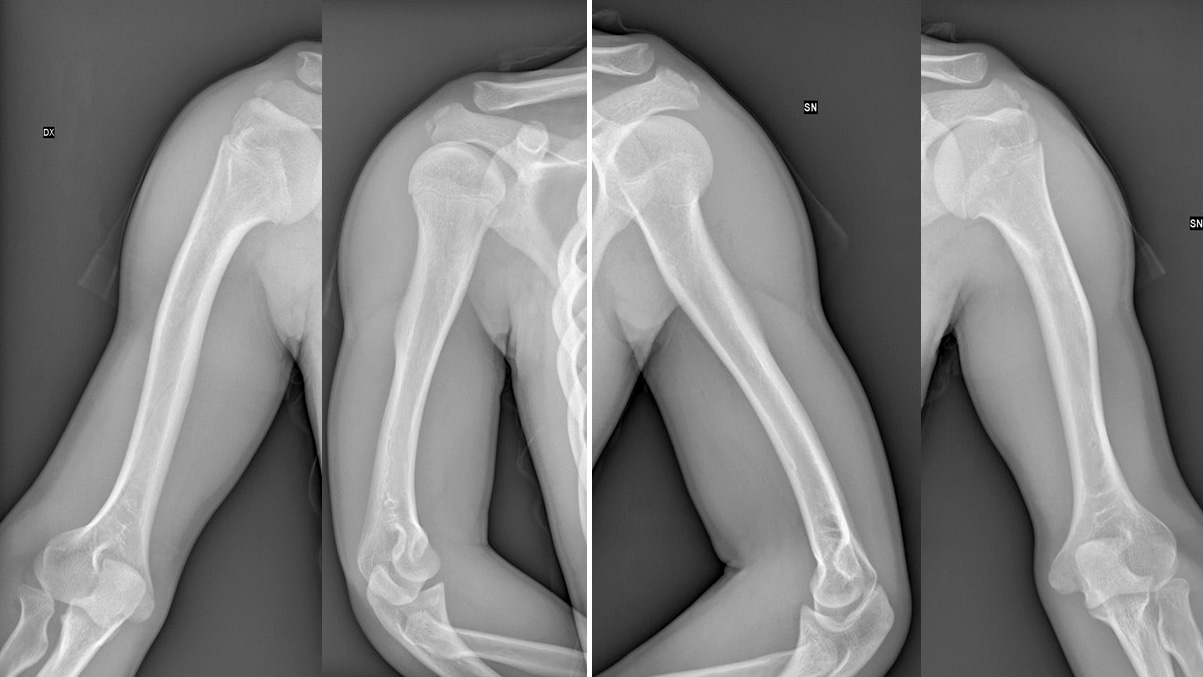

05 Ago Ipocondroplasia Cure: Allungamento bilaterale delle braccia in bambino

Allungamento bilaterale delle braccia con Ilizarov in bambino con ipocondroplasia: +8 cm e ripresa funzionale completa....